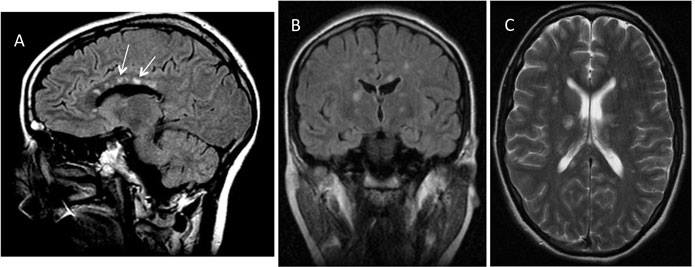

تم اكتشاف متلازمة سوساك وفقا لاشعة الرنين المغناطيسي على عينة من 15 مريضا، حيث كان هناك إصابات عديدة البؤر فوق الخيمة supratentorial، توجد في العديد من المرضى.

ومعظم الإصابات كانت صغيرة بمقياس يتراوح من 3 إلى 7 مم إلا أن بعضها كان أكبر من 7 مم.

وكان كل المرضى مصابين بإصابات في الجسم الثفني Corpus Callosum مع منظر مثقوب للخارج عند متابعة صورة الرنين المغناطيسي.

وتوجد الإصابات الثفنية في متلازمة سوساك بشكل مركزي. وبالمقارنة، فإن المرضى المصابين بالتصلب اللويحي والالتهاب الدماغي النخاعي المنتشر الحاد يملكون إصابات في السطح السفلي من الجسم الثفني.